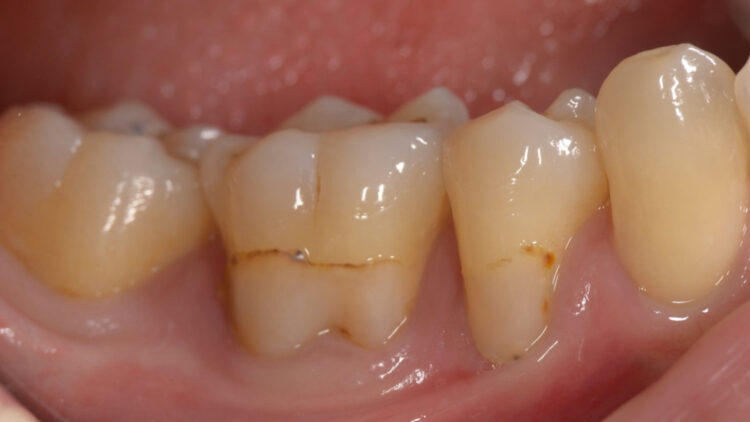

- 【術前】奥歯の歯肉退縮症例①